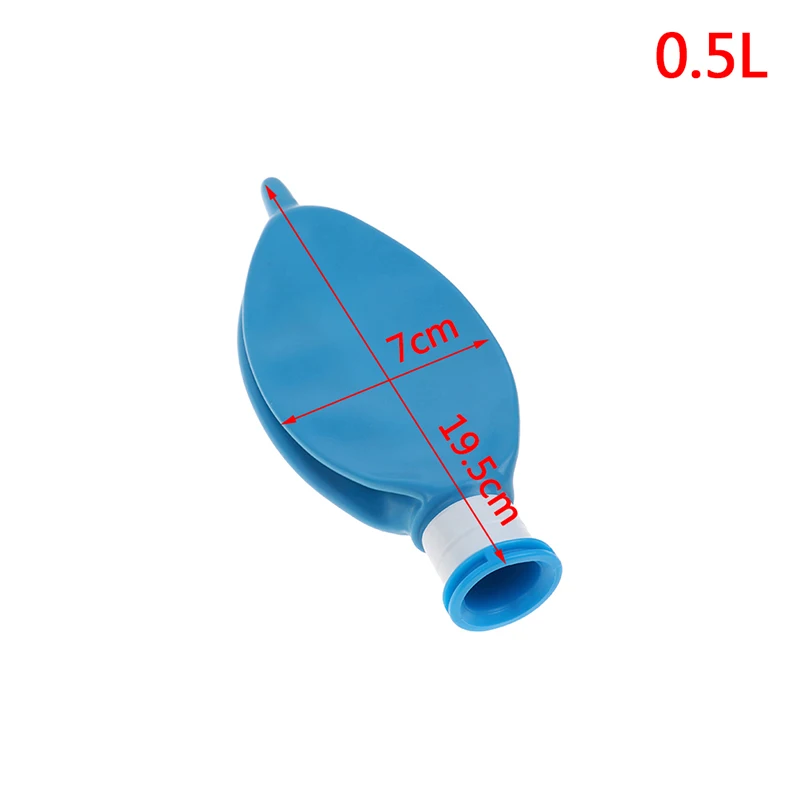

Описание:Материал: латексРазмер: 0.5л 1Л 2л 3лЦвет: синий

Примечания:Из-за разницы между различными мониторами изображения могут не отражать фактический цвет изделия.Сравните размеры деталей с вашими, пожалуйста, учитывайте погрешность в 1-3 см из-за ручного измерения.